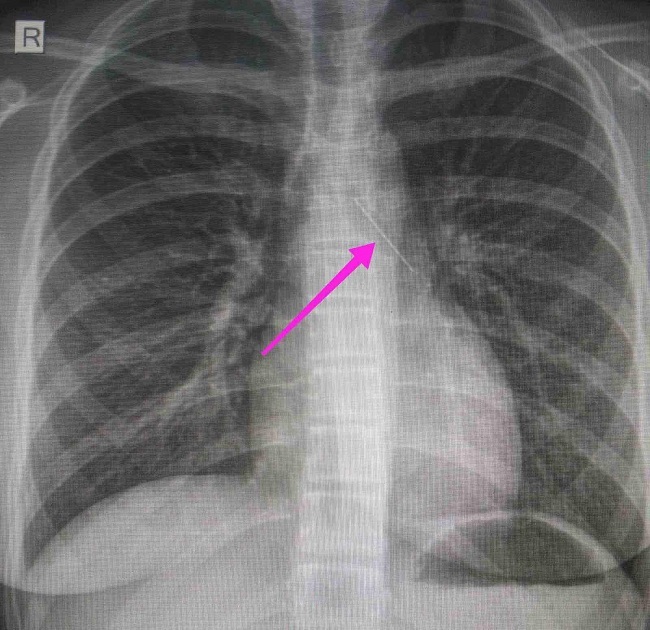

«Χθες 30/1/2022 στις 16:00 στο Τ.Ε.Π. του ΓΝΘ Ιπποκράτειο, προσήλθε ανήλικη συνοδευόμενη από τους γονείς της, μετά από αναφερόμενη κατάποση ξένου σώματος (καρφίτσα). Από την απεικονιστική διερεύνηση που πραγματοποιήθηκε με ακτινογραφία θώρακος αρχικά και ακολούθως με αξονική τομογραφία θώρακος, διαπιστώθηκε η ύπαρξη αιχμηρού μεταλλικού ξένου σώματος στην αναπνευστική οδό (αριστερός κύριος βρόγχος) και όχι στην πεπτική οδό.